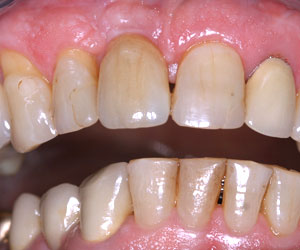

Un sourire retrouvé

Il vous manque toutes les dents

Vous souhaitez limiter l’inconfort de la prothèse complète mobile ? Deux implants à la mâchoire du bas pourront créer une rétention secondaire. Certes, vous restez en prothèse amovible, mais elle est stabilisée. Il s’agit du traitement minimal recommandé par un consensus médical de 2001 en cas d’édentement complet.

Vous pouvez bien entendu opter pour la réalisation d’un bridge ostéo-ancré fixe. Vous pouvez ainsi vous voir parler, chanter, rire, mâcher, éternuer sans que votre prothèse dentaire ne risque de se détacher. Vous avez choisi de la visser sur 4 implants au minimum.